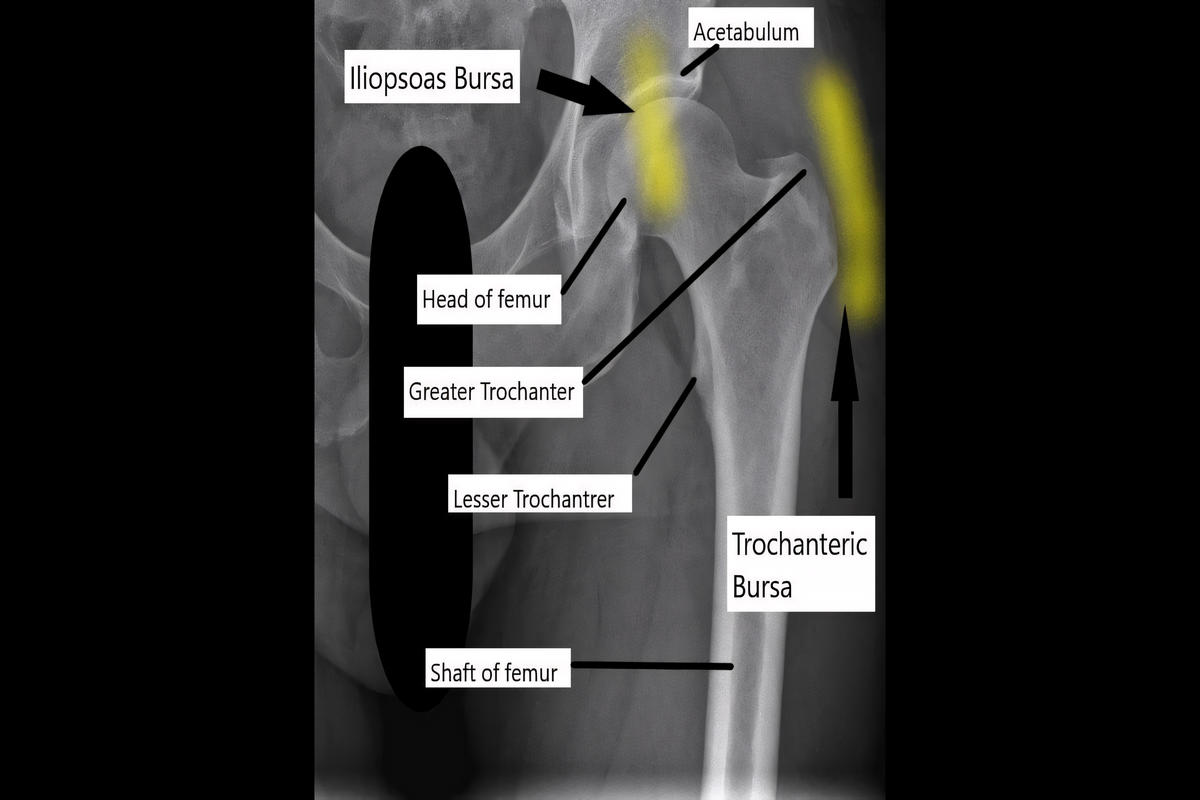

Η τροχαντήρια θυλακίτιδα ισχίου είναι φλεγμονή του ορογόνου θυλάκου που βρίσκεται πάνω από τον μείζονα τροχαντήρα του μηριαίου οστού. Ο θύλακος λειτουργεί ως προστατευτικό «μαξιλαράκι» ανάμεσα στο οστό και τους τένοντες, κυρίως του μέσου και του μικρού γλουτιαίου, μειώνοντας την τριβή κατά την κίνηση.

• Υπερηχογράφημα για εντοπισμό συλλογής υγρού ή τενοντοπάθειας

• Ακτινογραφία για αποκλεισμό οστεοαρθρίτιδας ισχίου